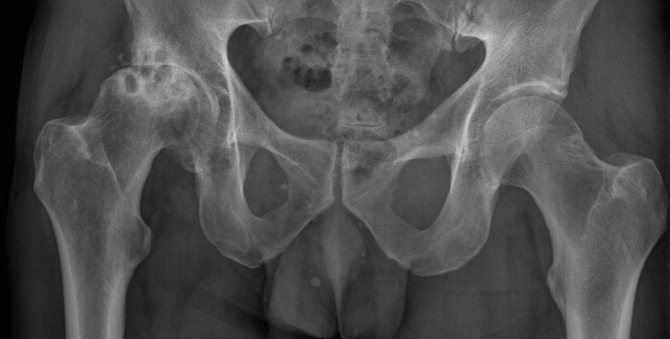

Коксартроз всегда диагностируется путем рентгена.

Справа на фото — головка ТБС, пораженная 3-й степенью коксартроза, когда уже никакое лечение не поможет.